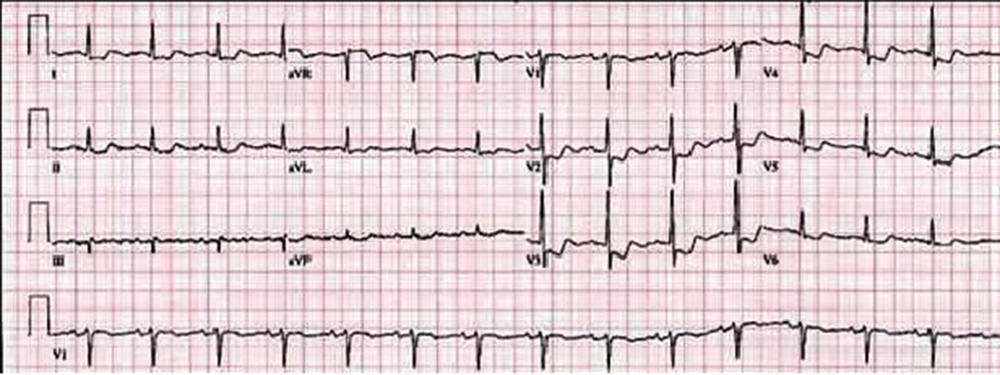

Στοπ εδώ, ακολουθεί εγκιβωτισμένη αφήγηση: Οι επόμενες δύο εβδομάδες από εκείνη την ημέρα, έχουν καταγραφεί στη μνήμη μου σαν fast track ταινιάκι, όχι και τόσο μικρού μήκους. Εγώ να παίρνω δρόμους και μαγαζιά, ρωτώντας μύστες και θεραπευτές, ψάχνοντας εναλλακτικές θεραπείες που να μη κοστίζουν τα μαλλιά της κεφαλής μου (δεδομένου ότι η λαπαροσκοπική εγχείριση καλυπτόταν στο 100% από την ασφάλεια που αδρά πλήρωνε η μανούλα μου τόσα χρόνια) και να μην θέλουν και 3 μήνες να δράσουν. Το αιώνιο πρόβλημα του χρόνου, με κυνήγησε κι εδώ. Μέσα στο διάστημα που η κάθε εναλλακτική θεραπεία θα χρειαζόταν για να δράσει, κάποια πέτρα θα μπορούσε να αποκολληθεί από την χοληδόχο κύστη να πάει ταξιδάκι στα ενδότερα μου, και να κινδυνεύσω να πεθάνω από Ίκτερο. Με χίλιους ανθρώπους μίλησα και χίλιες γνώμες πήρα. Χίλια ματζούνια, κουρκουμάδες, βότανα ήπια και ειδικά φαγητά έφαγα, μέχρι και μηλόξυδο πήγα και πήρα βιολογικό και το έπινα σε σφηνάκια. Δεν περίμενα αποτελέσματα σε δύο εβδομάδες. Δεν περίμενα όμως να αρχίσουν οι ταχυκαρδίες. Όχι ότι είναι στα συμπτώματα της χολολιθίασης. Είναι στα συμπτώματα της κάθε εμπειρίας που μας κάνει να νιώθουμε πιο κοντά στο θάνατο. Όταν φοβάσαι τον απρόσμενο σου θάνατο από μια παντελώς γελοία αιτία και πριν καν προλάβεις να φτάσεις τα χρόνια του Χριστού, η καρδιά σου πρέπει να μάχεται επί του μονίμου ενάντια στον άθλιο φόβο της λήξης. Έτσι κατέληξα να χάνω τον ύπνο μου από μόνιμες ταχυκαρδίες, και δεδομένων πολλών άλλων προβλημάτων που αφεντιά μου αντιμετώπιζε εκείνον τον καιρό, πέρα από τον ύπνο μου έχασα και τον ξύπνιο μου.

Είδα κι απόειδα να ηρεμίσω. Λουζόμουν με Λεβάντες, έπινα αφέψημα πασιφλώρας, χαμομήλια, βαλεριάνες και πάλι ήμουν στο τίποτα. Έπεφτα για ύπνο και με το που ξάπλωνα στο μαξιλάρι άρχιζε το μπαμ-μπαμ της καρδιάς μου, γιατί τικι-τακ δεν ήταν πια.

Μάλλον το ξέρετε κι εσείς, πως καλό είναι να μη κάνουμε ποτέ τέτοιες ερωτήσεις γιατί η πραγματικότητα είναι τέτοια ανακατώστρα που θα φροντίσει να μας έρθουν όλα πολύ πιο χάλια απ’ ό,τι θα μπορούσαμε ποτέ να φανταστούμε. Επίσης, όπως σίγουρα θα γνωρίζετε πολλοί (όσο πλήρως εγώ το αγνοούσα) το λεγόμενο προ-εγχειρητικό στάδιο, είναι το καλύτερα κρυμμένο μυστικό της ιατρικής κοινότητος. Σου λένε πως δήθεν θα έρθεις να κάνεις ένα μικρό check up, και καταλήγεις να κλαίς με νευρική κρίση έξω από το Ερρίκος Ντύναν, ουρλιάζοντας στην κακομοίρα τη μητερούλα σου που σε έπεισε να κάνεις όλη αυτή την παράνοια. Γιατί φυσικά, όχι απλά μου έκαναν καρδιογράφημα, όπως αρχικά ισχυρίζονταν πως θα γινόταν, αλλά μου πήραν αίμα και εννοείται πως λιποθύμησα όπως την πρώτη φορά. Η νοσοκόμα -που καλά έκανα τελικά και της είπα πως καμπουριάζει και πως πρέπει να κάνει ασκήσεις να ισιώσει- μου μπλάβιασε τη φλέβα μου ανεπανόρθωτα, μάλλον επίτηδες που την είπα καμπούρα. Σαν να μη μου έφτανε αυτό, μια άκρως σαδίστρια ξανθιά γιατρίνα πραγμάτωσε την φαντασίωση κάποιου άλλου πάνω μου, όταν με έβαλε να γδυθώ, χωρίς κανένα σεβασμό στα προσωπικά μου τμήματα, με έστησε μπροστά στο παλιό-μηχάνημα εκείνο που κάνει ακτινογραφίες, με διέταξε με πλήρως αυστηρό τόνο να μην αναπνέω καθόλου, και μόλις έσκασε η ραδιενέργεια, έτρεξε έξω από το δωμάτιο. Στα δύσκολα με άφησε μόνη και πιστέψτε με δεν διεγέρθην καθόλου.